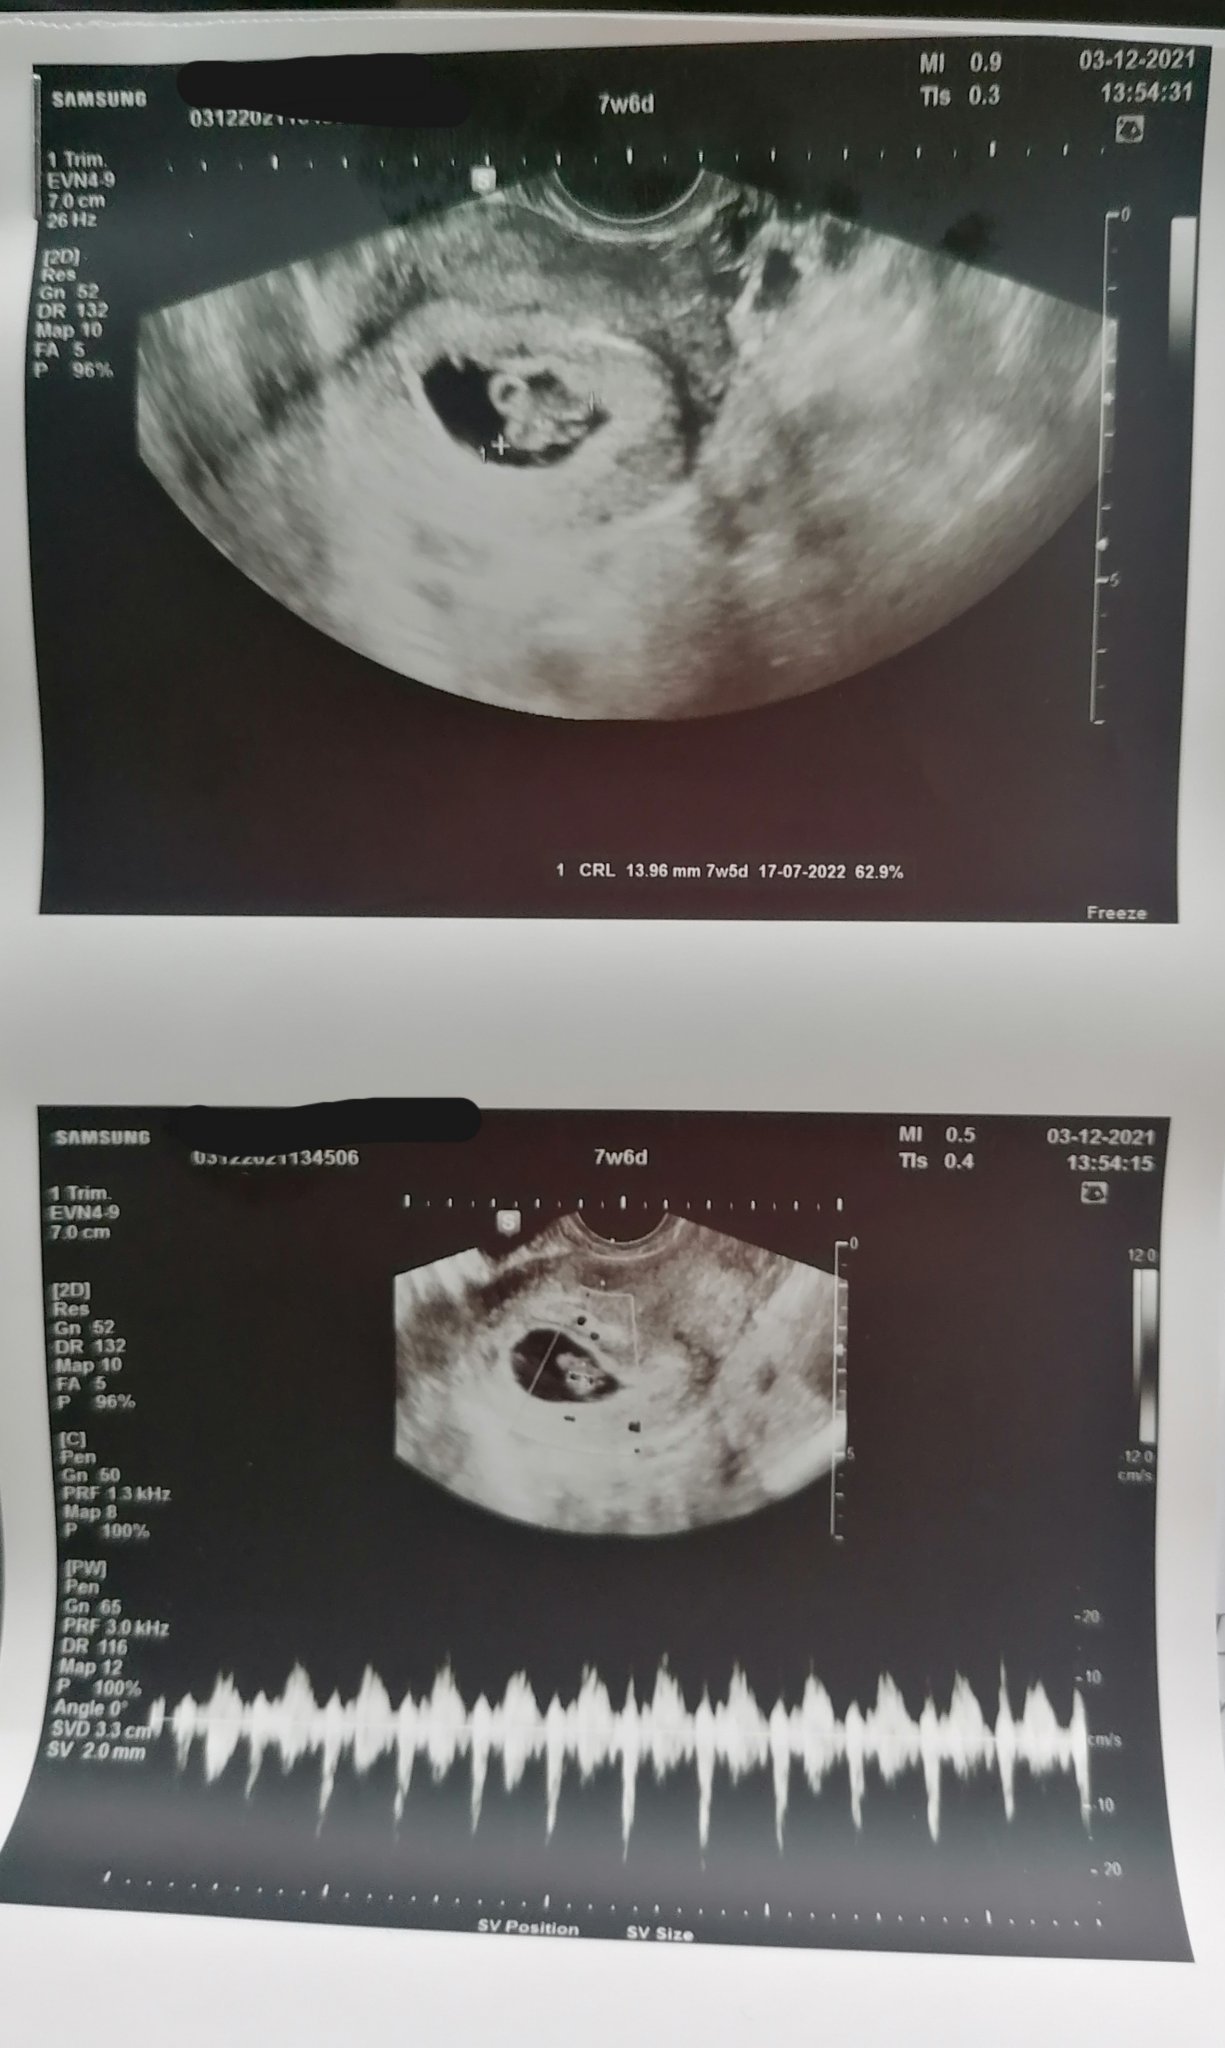

Последният ми преглед беше в 7 г.с и тогава определиха терминът за 06.07 Simple Smile

Терминът се определя на ранната фетална морфология и се фиксира тогава. Преди това е приблизителен и по-добре да се изчислява по ПРМ, ако цикълът е бил редовен. Първите седмици е нормално да се различава с няколко дни, като има значение дали е с вагинален или коремен ехограф (първия е по-меродавен). Иначе ултразвука не представлява никаква опасност за бебето, това не е рентген.

включвам се отново след прегледа ми днес, за да се похваля, че всичко е наред, дори чухме и сърчицето. Heart

От зацапването няма и следа, няма и никакви проблеми. За 2 седмици сме пораснали с 11мм. Grinning Успешна бременност на всички! Blush